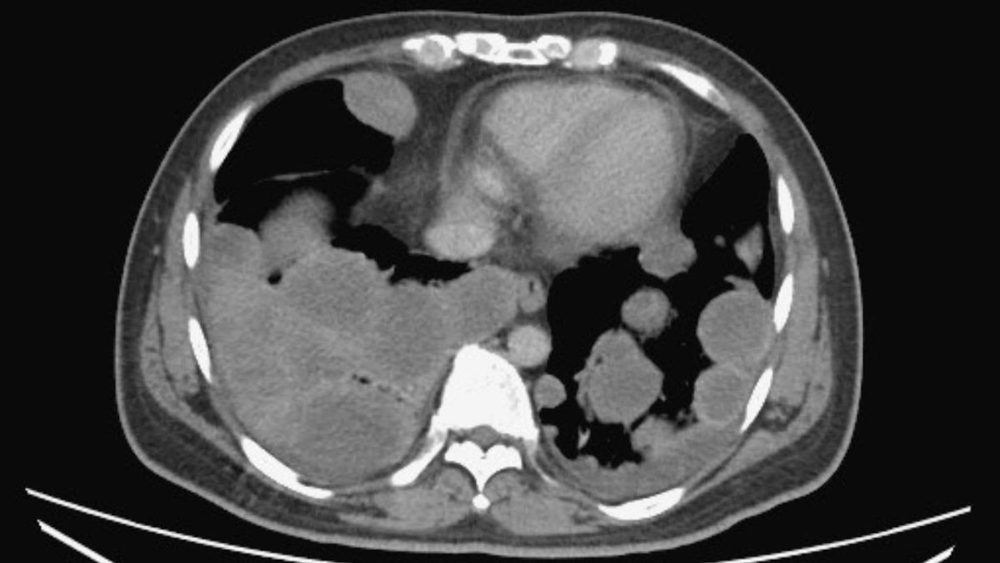

院方安排X光及电脑断层扫描后,发现其体内多处已有肿瘤扩散,涉及肺部、肝脏及后腹腔。医疗团队进一步追查后确认,病灶源头来自左侧睾丸一个约5.5公分的恶性肿瘤,而后腹腔另有一个高达12公分的巨大肿瘤,已属睾丸癌晚期并出现广泛转移。